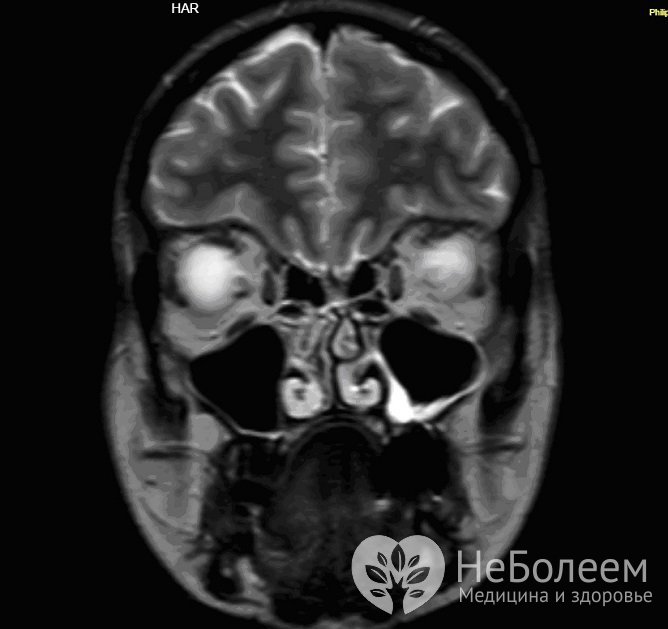

Для уточнения диагноза может быть назначена магнитно-резонансная томография гайморовых пазух Для уточнения диагноза может быть назначена магнитно-резонансная томография гайморовых пазух

Особую информационную ценность в распознавании патологии гайморитов представляет эндоскопическое исследование синуса, а также КТ и МРТ (компьютерная и магнитно-резонансная томография). С помощью КТ удается точно определить характер и распространенность патологического процесса, степень вовлечения костных и мягких тканей пограничных областей.